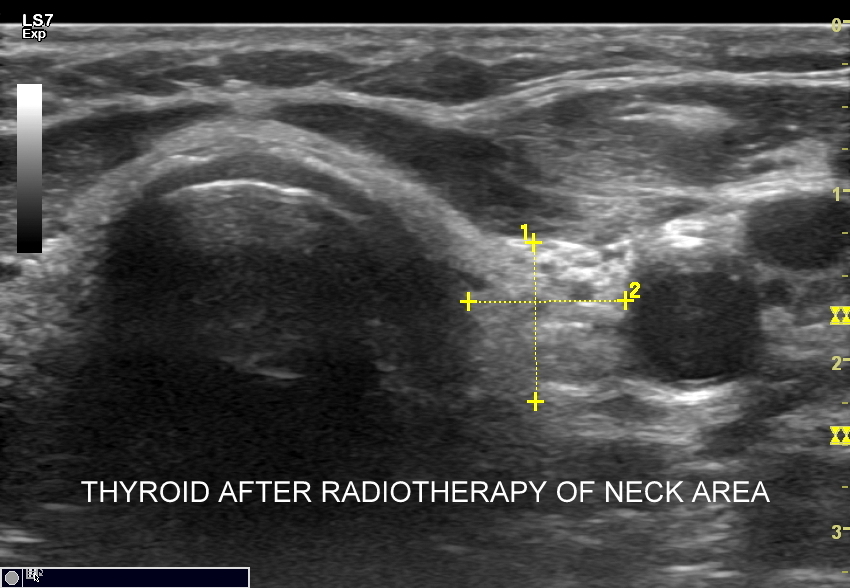

6. Starzenie i zmiany wsteczne narządów szyi w USG: blizny, zwłóknienie, stłuszczenie, zaniki, zwyrodnienia.

Multiparametryczne badanie USG (MPUS) jest rozwinięciem klasycznego USG tarczycy i szyi pod postacią jednoczasowego zastosowania różnorodnych technologicznie trybów obrazowania USG, zarówno tzw. „nowych”, jak i „starych”. Wśród nowych najważniejszym jest obrazowanie mikrounaczynienia (MVI / MVF), w dalszej kolejności tryb elastograficzny oraz B-flow. Wymienione „nowe” modalności w połączeniu ze „starymi”, przede wszystkim z Dopplerem spektralnym i color-Dopplerem, stanowią rdzeń nowoczesnej ultrasonografii MPUS, gdyż umożliwiają pozyskanie znacznie większej ilości informacji z badania USG szyi w porównywalnym przedziale czasowym, a przez to uzyskanie jego większej wartości diagnostycznej.